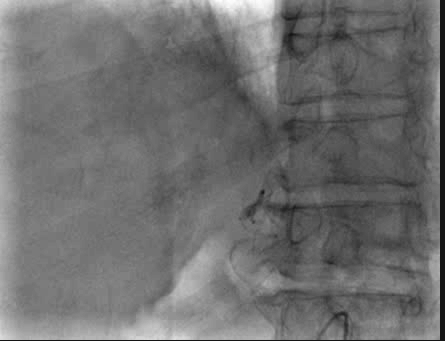

手术过程

术中造影发现肿瘤巨大,染色明显,微导管超选至其中几支肿瘤供血动脉后,予表柔比星80mg+聚乙烯醇栓塞微球(蓝色型,100-300um)、5支无色型(300-500um),1支无色型(500-700um)栓塞肿瘤供血动脉,直到栓塞至肿瘤血管血流停滞。